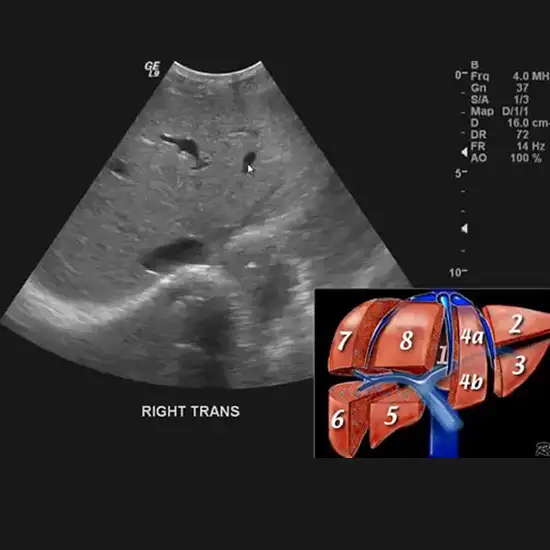

Abdominal ultrasound is a safe imaging test used to diagnose a variety of medical issues of abdomen area. It is quick and nearly painless. It makes no use of radiation. This test detects both routine and potentially hazardous conditions.

To diagnose problems such as abdominal pain, bloating, or bowel irregularities, an abdominal ultrasound examination is required. It can also detect cancer, kidney or gallbladder stones, fatty liver, and other serious illnesses. It is also used to diagnose conditions such as enlarged organs, abdominal fluid, gallstones, hernia, pancreatitis, kidney disease, liver cancer, and appendicitis.